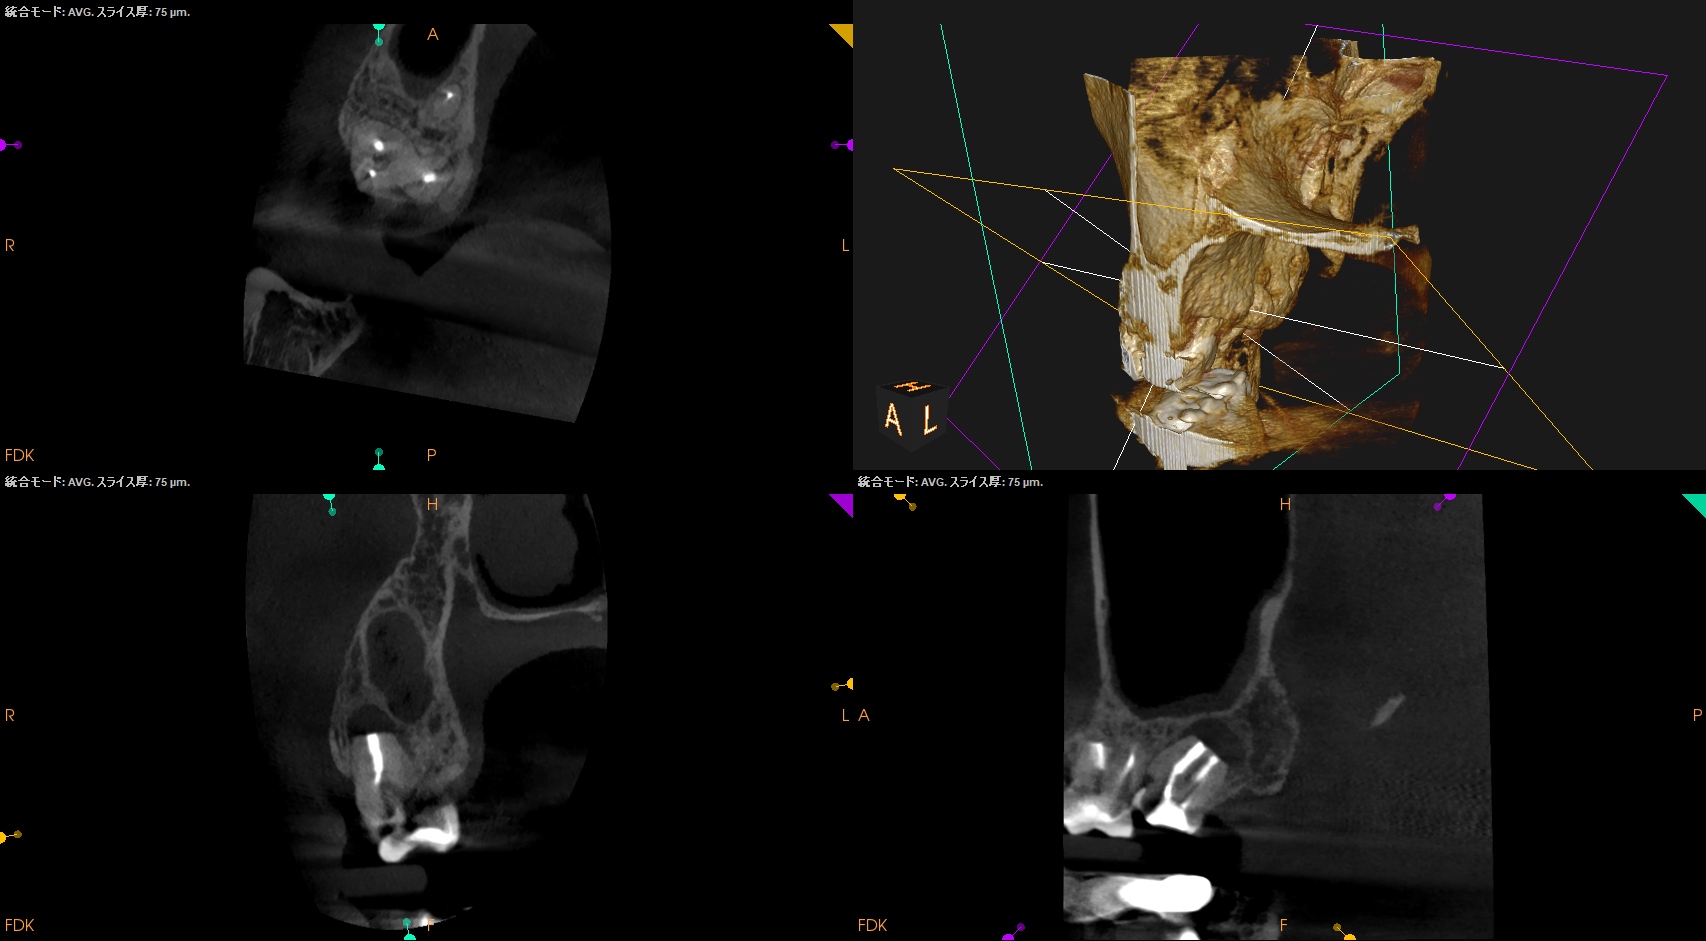

術後に口腔内PA, CBCTも撮影した。

MB

DB

P

ということで問題が客観的にないことがわかる。